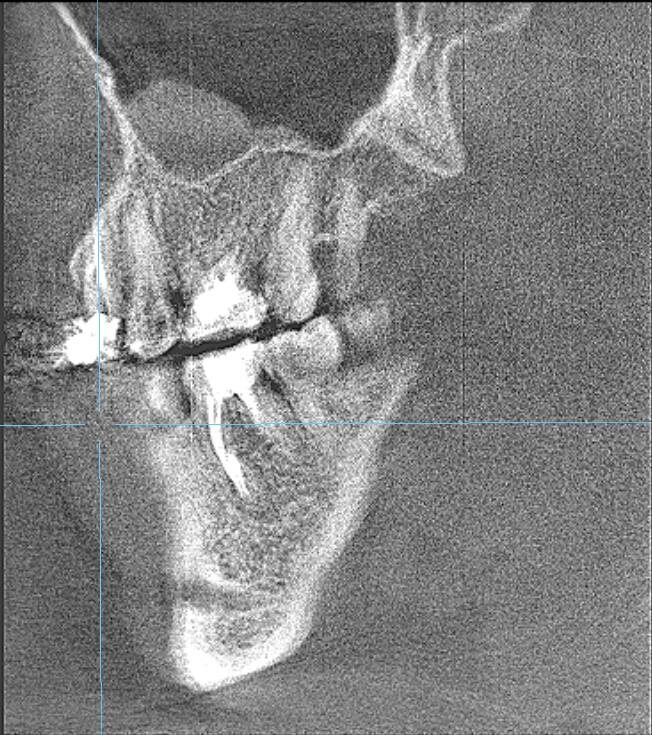

Π― сдСлала ΠšΠ›ΠšΠ’. ЧСстно скаТу Π½Π°Π΄Π΅ΠΆΠ΄Ρ‹ Π±Ρ‹Π»ΠΎ ΠΌΠ°Π»ΠΎ...ΠžΡ‡Π°Π³ воспалСния впСчатлял ΠΌΠ°ΡΡˆΡ‚Π°Π±Π°ΠΌΠΈ. Π― прямо сказала ΠœΠ°Ρ€ΠΈΠΈ: ΡˆΠ°Π½ΡΡ‹ Ρƒ Ρ‚Π°ΠΊΠΎΠ³ΠΎ Π·ΡƒΠ±Π° 50 Π½Π° 50, Π½ΠΎ ΠΏΠΎΠΏΡ€ΠΎΠ±ΠΎΠ²Π°Ρ‚ΡŒ ΠΌΠΎΠΆΠ½ΠΎ πŸ€”

ΠŸΡ€ΠΎΡˆΡ‘Π» Ρ†Π΅Π»Ρ‹ΠΉ Π³ΠΎΠ΄...И Π²ΠΎΡ‚ ΠΎΠ½Π° снова Π² ΠΌΠΎΡ‘ΠΌ расписании. Π”Π΅Π»Π°Π΅ΠΌ ΠΊΠΎΠ½Ρ‚Ρ€ΠΎΠ»ΡŒΠ½ΡƒΡŽ ΠšΠ›ΠšΠ’ ΠΈ видим… ΠΏΠΎΠ»Π½ΠΎΠ΅ Π·Π°ΠΆΠΈΠ²Π»Π΅Π½ΠΈΠ΅ ΠΎΡ‡Π°Π³Π°!Ни слСда воспалСния!